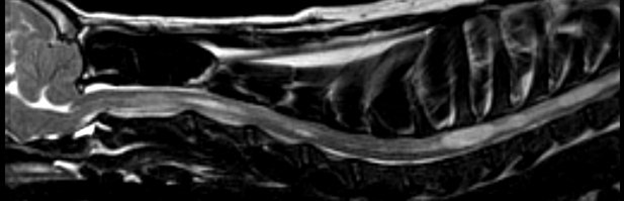

8 years old

No symptoms of SM whatsoever

Very mild malformation, slight

squashing/pinching of cerebellum

No herniation

Medulla almost normal

Very slight dilatation of central canal

in one tiny area